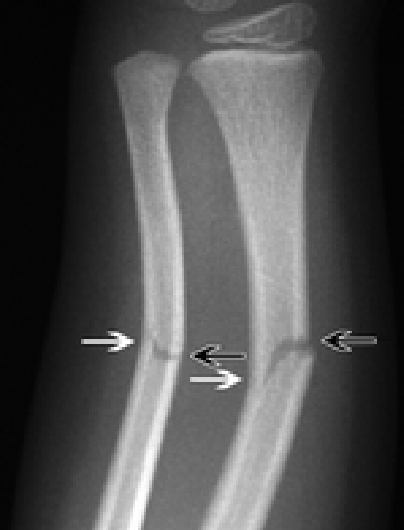

Radiographic Types of nonunion

Hypertrophic Rich blood supply Hypotrophic Poor blood supply

31

Hypertrophic Rich blood supply

Elephant  Horse hoof  Oligotrophic

32

Hypotrophic Poor blood supply

Torsion wedge  Comminution  Defect  Atrophic